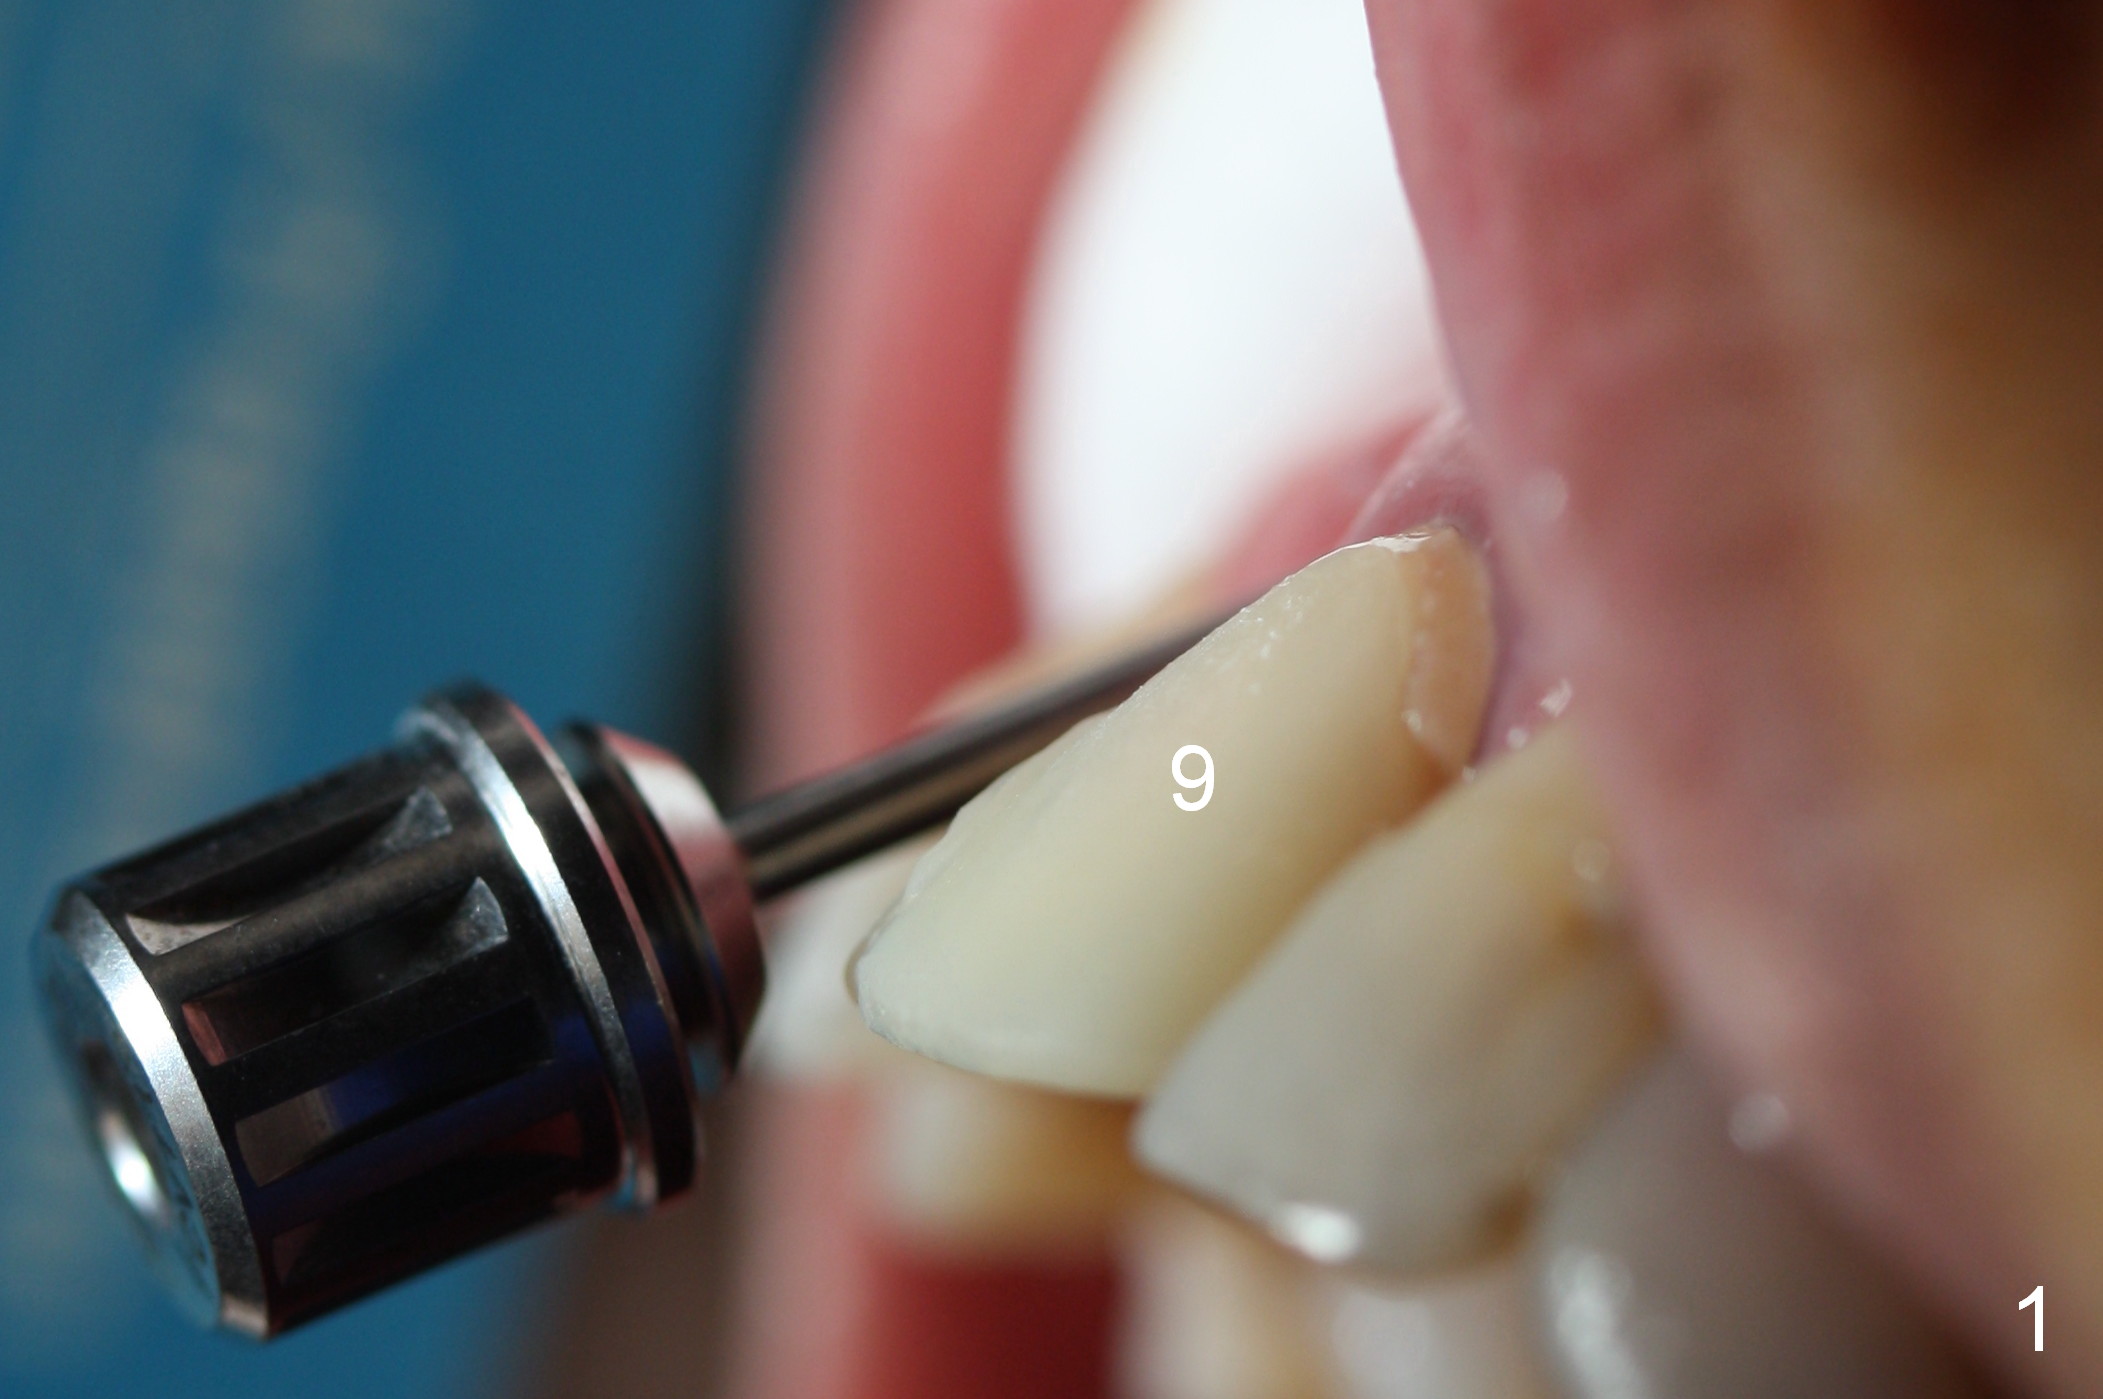

The patient returns for Zirconium abutment retrieval 1 month post its fracture.  When the provisional is removed, the gingival pontic morphology remains (Fig.2).  There is no problem to remove the abutment screw (Fig.1 with its driver), whereas it is difficult to remove the remaining abutment (Fig.2 *) due to limited access.  When the access improves by incision (Fig.3), buccal implant thread exposure is confirmed and the fractured abutment (*) is to be removed easily.  A 15° angled abutment (A) corrects the angulation, but not the position (Fig.4,5, compare to Fig.1 with a driver in place).  After being trimmed, the labial contour of the abutment is equivalent to that of #9 (Fig.6,7), but the margin is higher.  Using an abutment with taller gingival height (from 2 mm to 3 mm) may alleviate the margin issue.